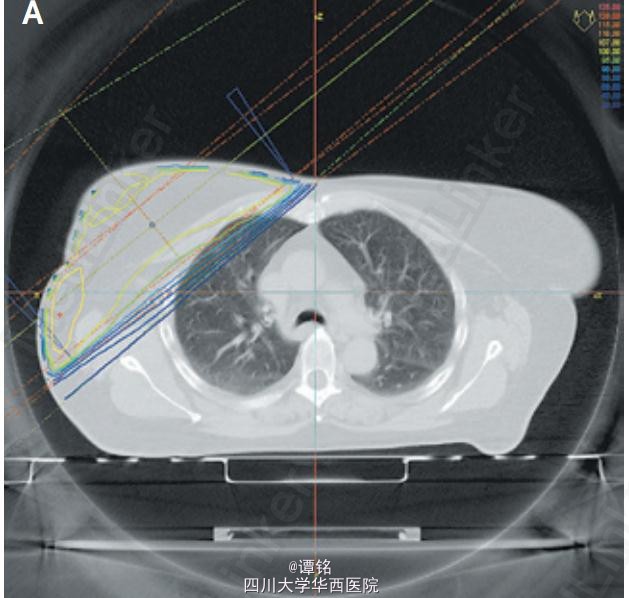

患者为58岁女性,因呼吸困难、咳嗽2周入院。8月前因右侧乳腺 I 期肿瘤(T1N0M0)行乳腺肿物切除术及辅助放疗,5周内患者共接受了总剂量为50 Gy的放疗,照射区域包括乳腺实质和部分前肺,见CT中的等剂量线(图A),6月前完成放疗。